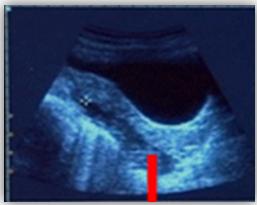

与hCG结合更有意义 ——血hCG≥2000IU/L时,若未见宫内妊娠囊,高度怀疑异位妊娠。 宫腔内空虚,宫旁出现低回声区,其内探及胚芽及原始心管搏动 ——可确诊异位妊娠。